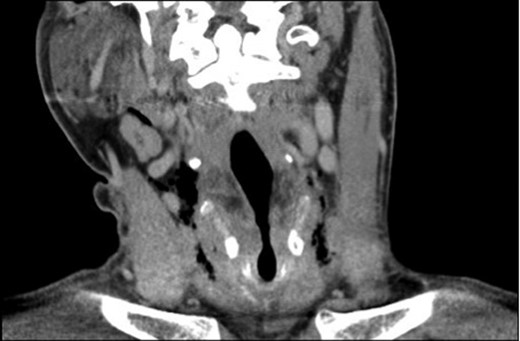

A 39-year-old male patient with a background of type II diabetes, spina bifida and meningocele hydrocephalus presented to the emergency ENT clinic with a 2-day history of a throat complaint. He described that while hyperextending his neck to finish his cup of coffee he felt a sudden crack in the middle and central portion of his throat. This crack produced a sound that was also heard by his partner on the other side of the room. The patient subsequently experienced a spontaneous coughing fit. During the history, he described pain over the thyroid cartilage, odynophagia, pain on moving his neck and a hoarse voice. He also described the sensation of having something flapping in his throat while breathing. He denied any recent history of throat trauma and had no other ENT complaints. On examination he had a tender thyroid cartilage with palpable crepitus of the thyroid cartilage when balloting it between the fingers of each hand. There was no palpable surgical crepitus of the soft tissues of the neck and no lymphadenopathy. Flexible fibre optic nasendoscopy allowed dynamic and real-time evaluation of the vocal cords and revealed significant bruising and swelling of the right arytenoid cartilage. Potential cord avulsion or paralysis was not identified. A computed tomography (CT) scan was subsequently arranged to further assess the laryngeal anatomy and was reported to show locules of free air in the soft tissues of the neck with generalized oedema of the paraglottic tissues (Fig. 1). There was no fracture of the cartilage. The patient was admitted for strict airway observation, given a stat dose of IV steroid and started on IV antibiotic to cover supraglotittis. Blood biochemistry and haematology samples were normal, with the exception of the C-reactive protein (a marker of inflammation), which was 58 mg/l. Repeat nasendoscopic examination the following day showed that the bruising had migrated into the right vocal fold and a new fullness in the left pyriform fossa. By Day 3 following admission the nasendoscopic examination was improving to normal and the right arytenoid cartilage was seen to be less floppy. By this time the patient's pain was settling, although the hoarseness of voice was still present. He was discharged with 7 days of oral antibiotics and was reviewed in ENT clinic at 1 week where, although his voice was still hoarse, the nasendoscopic examination was normal. By 6 weeks, the voice had settled, the thyroid cartilage crepitus was gone and the larynx had returned to normal.